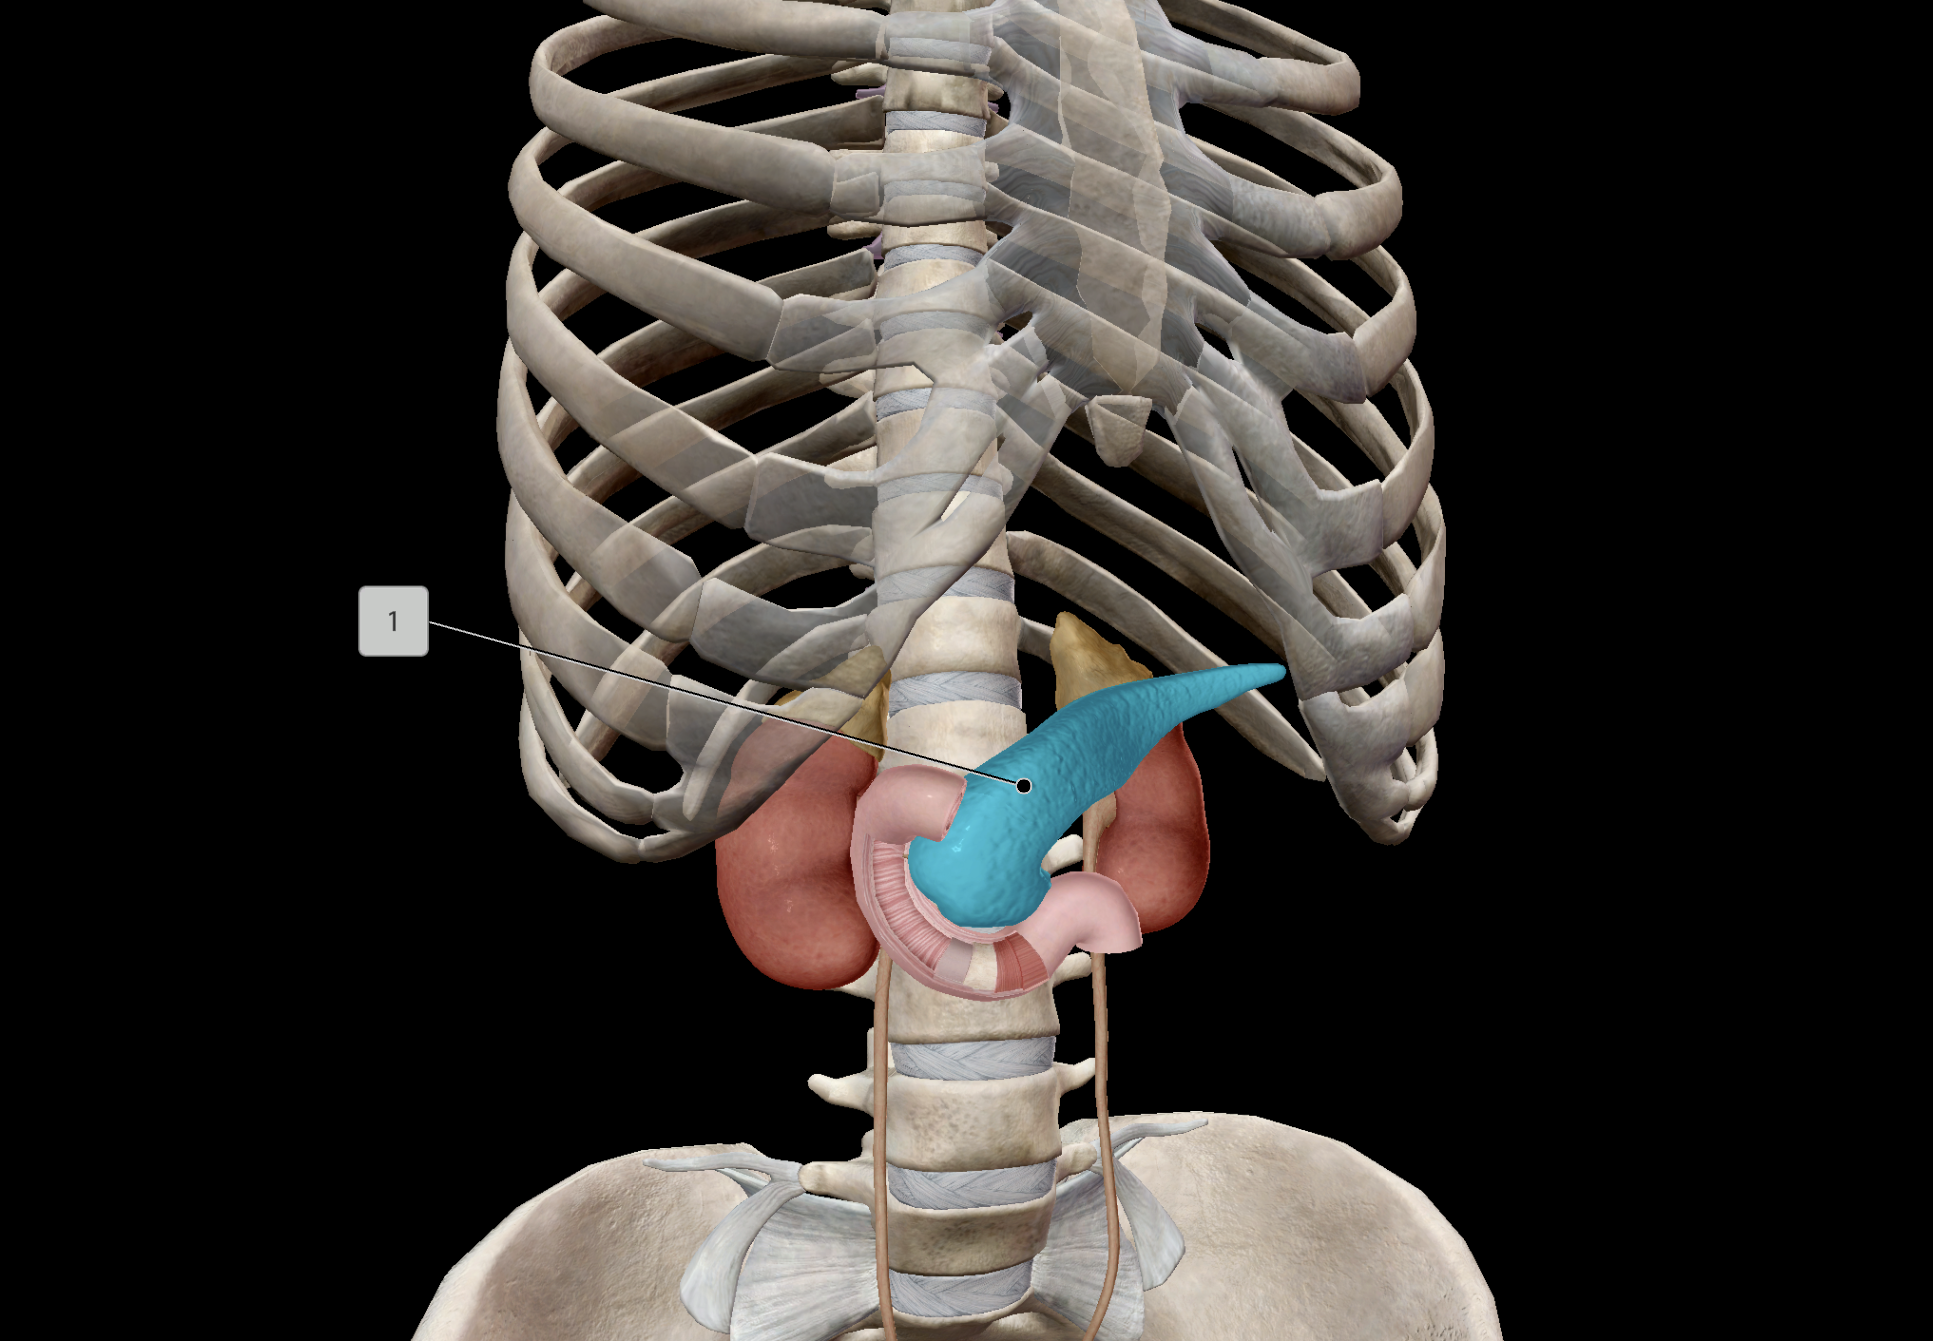

Pancreas